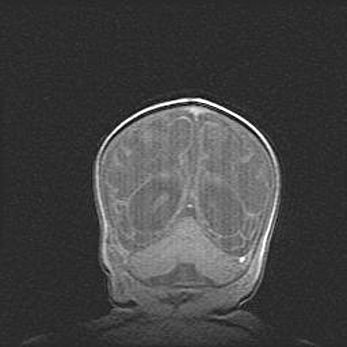

Мальформация Денди-Уокера. Киста задней черепной ямки.

Агенезия мозолистого тела.

Возраст: 2,5 месяца

Вес: 2420 г

Пол: женский

Окружность головы: 37 см

Срок гестации: 32 недели

Мальформация Денди—Уокера — редкий вид патологии ЦНС, представляющий собой врожденный порок развития каудального отдела ствола и червя мозжечка, ведущий к неполному раскрытию срединной (Мажанди) и латеральных (Лушка) апертур IV желудочка мозга. Для этогно синдрома характерна триада симптомов: гипотрофия червя мозжечка и/или полушарий мозжечка, кисты задней черепной ямки, гидроцефалия различной степени. В 70% случаев порок сочетается и с другими аномалиями головного мозга, в частности с агенезией мозолистого тела.